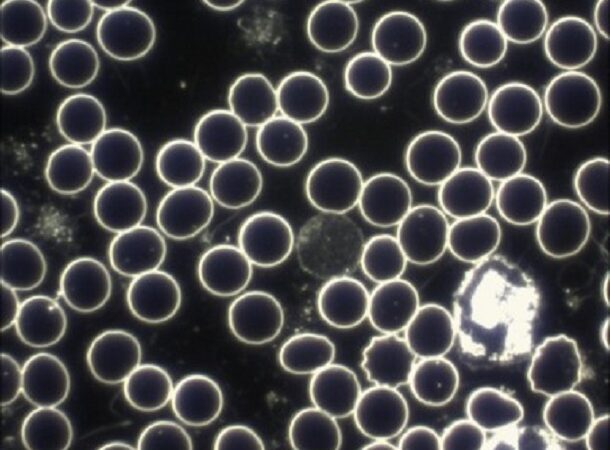

Dunkelfeldmikroskopie – Was ist das? Beispiel und Unterschied zur “normalen” Mikroskopie

Bei der Dunkelfeldmikroskopie handelt es sich um ein realtiv beliebtes Diagnoseverfahren in der Alternativmedizin. Bekannt wurde es in der Humanmedizin durch den Zoologen und Entomologen Prof. Dr. Günther Enderlein. Die Dunkelfeldmikroskopie gehört zunächst einmal in die Verfahren der Durchlichtmikroskopie. Anders als in einem Hellfeldmikroskop kann man die Dunkelfeldmikroskopie eher mit der Sicht in einer sternenklaren …